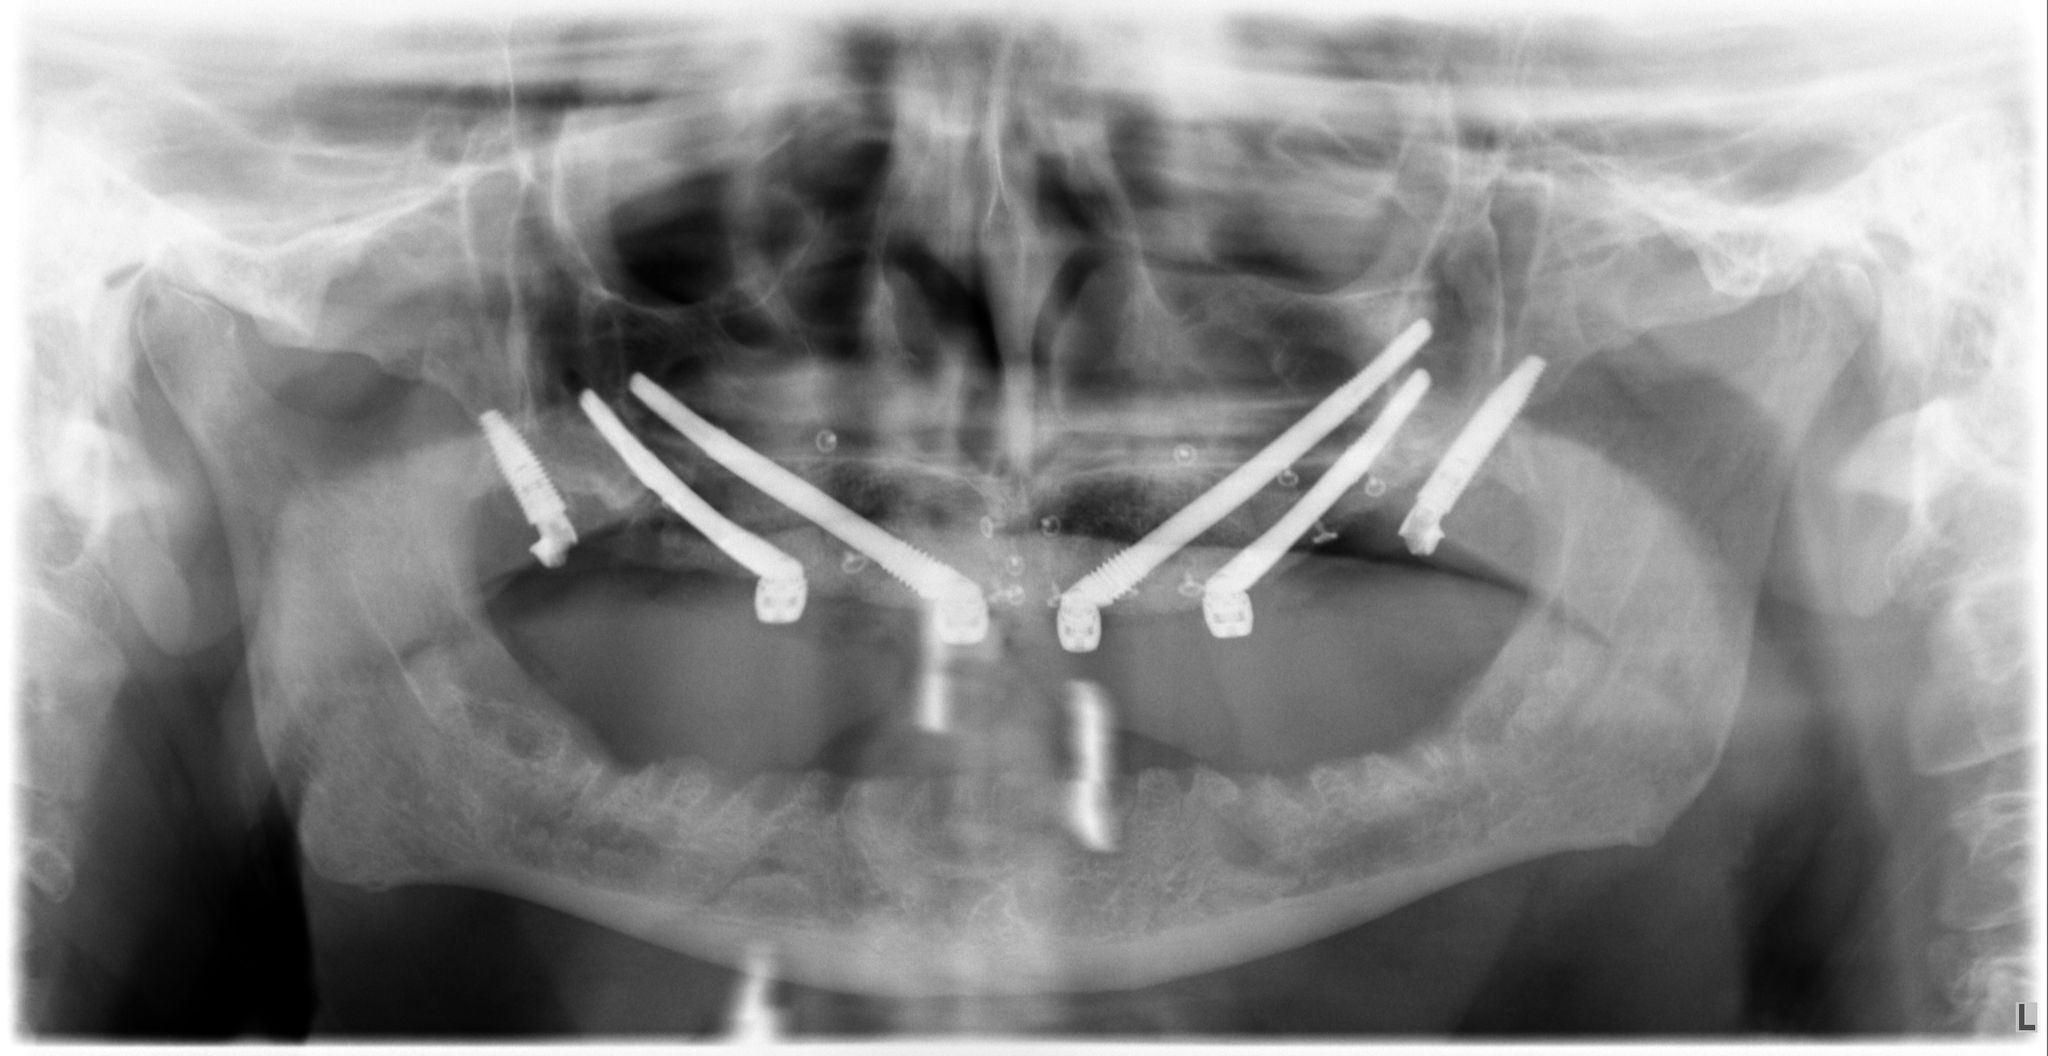

2. Implantes Pterigoideos

Se colocan en la parte más posterior del maxilar superior, anclándose en las apófisis pterigoides del hueso esfenoides. Son fundamentales para rehabilitar la zona de los molares (donde masticamos con más fuerza) sin necesidad de realizar elevaciones de seno maxilar. Aportan una estabilidad posterior crítica para la durabilidad de la prótesis.

- Planificación digital y cirugía guiada para máxima precisión.